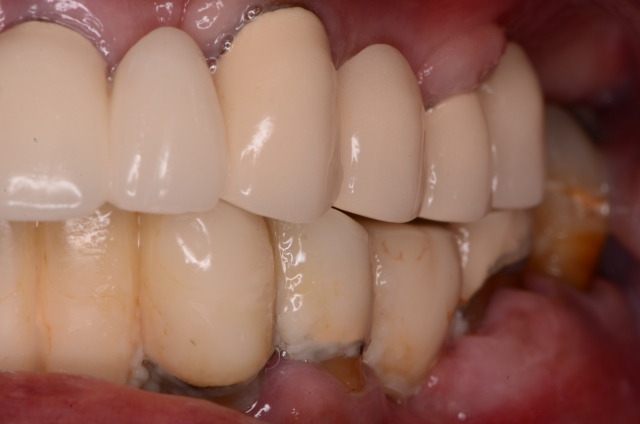

Many of our immediate fixed hybrid patients begin as emergency patients seeking relief from pain. Some begin as new patients unaware of their dental condition. Many patients are unaware of their true dental condition. Photography is the primary way to communicate this reality in an efficient and effective manner. Once we’ve taken the photos and examined radiographs, we can better assess their overall condition. Having the photos for the patient to see is the game-changer. Like the old adage states: “A picture is worth a thousand words.” Once the photos are there, you now have an effective platform upon which you can discuss findings that may warrant a more comprehensive examination.

Photography is the linchpin of the entire co-discovery process. We take six pictures in every new case. Spear teaches that these are the six images that will improve case acceptance. Here’s an example:

If you are not yet taking 35 mm photography of your patients, this is a great time to start. Photographs will not only prove invaluable to you as a clinician but will also affect your patient’s perception of their own oral condition very quickly. The effect can be miraculous. Many times a patient will say to me, “Are those my teeth?”

Rampant root caries, extreme worn dentition and the corrosive effects of GERD are all effectively demonstrated with these photos. These photos get the ball rolling on patients requiring more comprehensive treatments due to a terminal dentition.